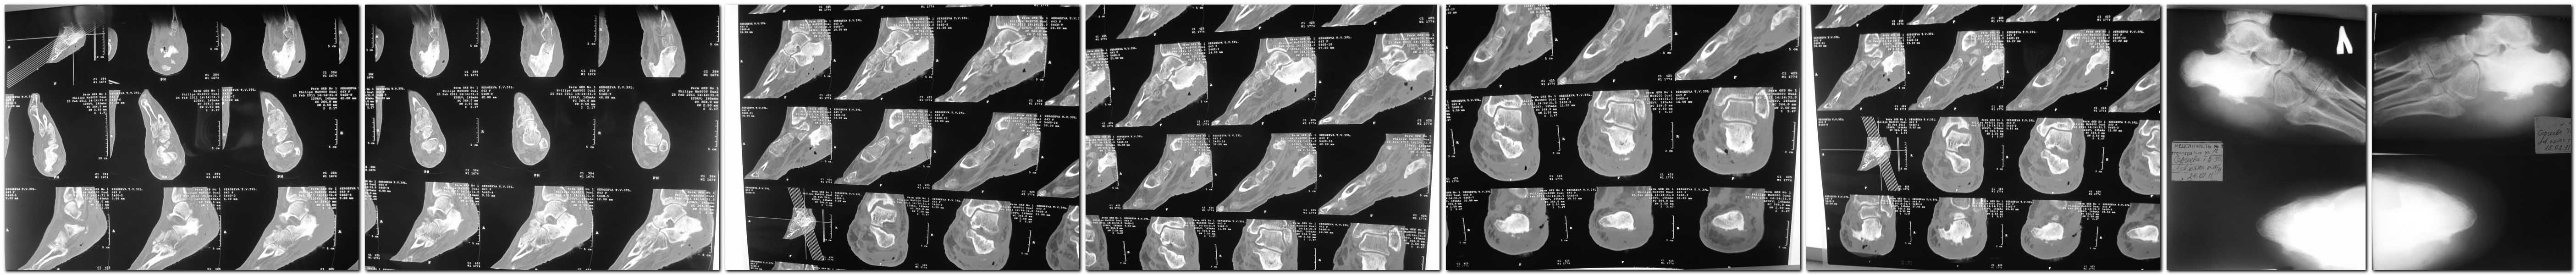

получше разрешение у КТ и Р-грамм

доброго времени суток коллеги. ВЫклаываю фотографии стопы как есть сейчас. прошу заранее прощения, что выкладываю фото через большой временной промежуток.